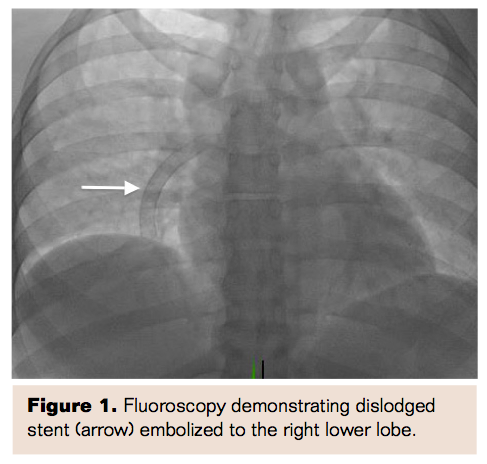

Access was obtained in the right femoral vein, and iliocaval venogram revealed brisk flow with no evidence of thrombosis and normal caliber iliac veins. A balloon-tipped PA catheter was used to demonstrate elevated right heart pressures with PA mean pressure of 35 mmHg. Angiogram of the PA confirmed the presence of a stent lodged in the right lower lobe branch of the PA (Figure 3). A 7 Fr Pinnacle Destination sheath (Terumo) was then advanced selectively into the right PA, and a 25 mm Gooseneck snare (Covidien) was used to capture the embolized stent edge (Figure 4a). Persistent negative backward pressure on the snare with concurrent positive forward pressure on the sheath was utilized to gradually retrieve the embolized stent into the sheath (Figure 4b) and subsequently externalized from the sheath (Figure 5). Repeat selective PA angiogram revealed persistent clot burden in the right lower lobe branch of the PA (Figure 6). An ultrasound-enhanced thrombolysis catheter (EkoSonic Endovascular System; BTG International) was positioned within the right lower lobe branch of the PA and catheter-directed thrombolysis (CDT) initiated at 1 mg/hr of tPA infusion through the catheter (Figure 7). The thrombolysis catheter was removed after 24 hours and the patient subsequently initiated on anticoagulation with warfarin and discharged home when therapeutic levels had been reached. She was seen in follow-up in 1 month when a repeat CT revealed resolution of the pulmonary embolism (Figure 8) and no residual injury from the embolized stent.